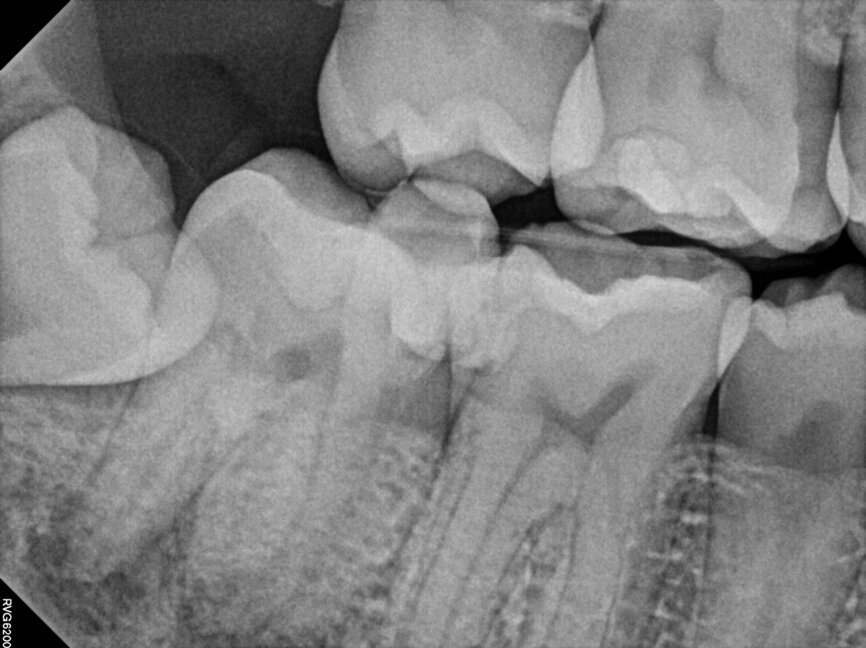

Fig. 14a: Case treated with Bassi Logic controlled memory nickel titanium files. Note the visualization of the third root on this lower molar and conservative canal preparation shape. (Courtesy of Dr. Alex Chan)

Fig. 14b: Case treated with Bassi Logic controlled memory nickel titanium files. Note the visualization of the third root on this lower molar and conservative canal preparation shape. (Courtesy of Dr. Alex Chan)

There are literally dozens of instrumentation systems available globally at this time. One author uses the Twisted File (KavoKerr) (BG) and the other Logic (Bassi Endo) (RM). This notwithstanding, the goals of canal shaping are identical regardless of the system used. Regardless of the instrumentation system used, patency is always sought during canal scouting and instrumentation. Clinicians can debate the relative merits of reciprocation versus rotary motion, optimal Af temperatures (austenite transformation temperatures that control whether a file undergoes the martensitic transformation), controlled memory files ground by CNC machines vs. twisting nickel titanium in R phase along with a multitude of different similar clinical issues. Regardless of these nuances, it is the adherence to basic principles of canal preparation that files create a pathway from coronal to apical to allow irrigant to flow into all of the canal ramifications which clean the root canal system and optimize clinical success.

Goals of canal preparation include keeping the canal centered in its original position within the root structure and keeping the apical foramen at its original position and size. One of the hallmarks of all the cases illustrated is that the apical foramen has been respected. Specifically, it has not been moved, transported, zipped and/or altered in any way. The apical foramen might be thought of as the “North Star” in endodontics. Reaching the apical constriction without transporting the canal and eliminating all debris from the canal and providing a tapering funnel from orifice to apex is a key canal preparation objective.

The final prepared canal shape should be large enough to irrigate and obturate, but not so large as to structurally weaken the tooth. For practical purposes, while treatment philosophies differ, the minimum guidelines for final prepared taper should be .04 and the minimum apical diameter a 30 (depending on the initial size of the foramen). Given the advent of controlled memory nickel titanium there is little indication for larger tapers, especially in fine three-dimensional apical curvatures. As mentioned, patency is essential because its obtainment means that the clinician can always reach the apex during every phase of treatment and its loss means that tissue, toxins and bacteria can remain despite irrigation procedures, especially in the apical third. Apical debris is the harbinger of iatrogenic events including but not limited to canal transportation, zipping, irrigant extrusion and a lack of optimal canal cleaning.